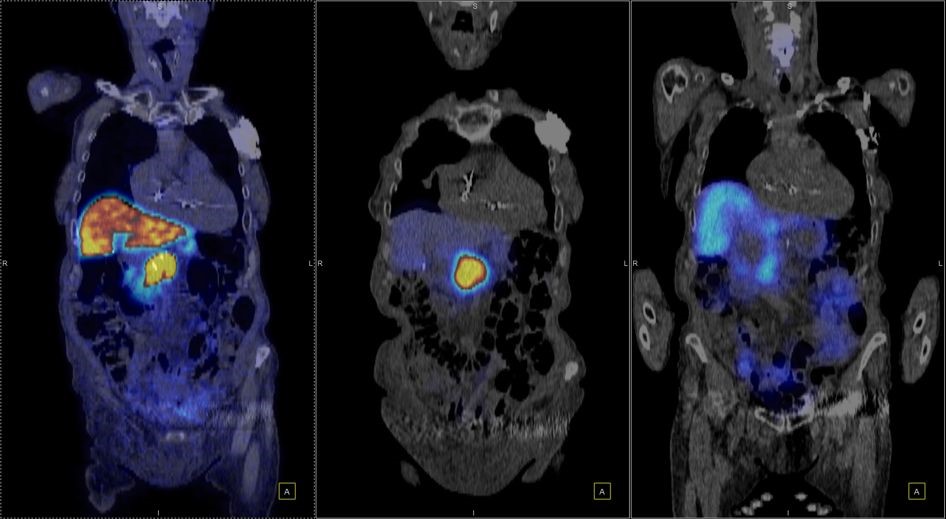

Η θεραπεία με Lu-177 DOTATATE (PRRT – Peptide Receptor Radionuclide Therapy) αποτελεί μια από τις πλέον εξελιγμένες μορφές στοχευμένης ραδιονουκλιδικής θεραπείας για νευροενδοκρινείς όγκους του γαστρεντερικού και του παγκρέατος, αξιοποιώντας την υπερέκφραση των υποδοχέων σωματοστατίνης στους νεοπλασματικούς ιστούς. Η διαδικασία περιλαμβάνει τον ακριβή προσδιορισμό της έκτασης της νόσου μέσω Ga68 DOTATATE PET/CT, την επιβεβαίωση υψηλής έκφρασης υποδοχέων SSTR και στη συνέχεια τη χορήγηση του Λουτέσιο-177 DOTATATE, το οποίο δεσμεύεται εκλεκτικά στους ανωτέρω υποδοχείς. Η ενέργεια του β-εκπομπού Λουτέσιου επιτρέπει στοχευμένη κυτταροτοξική δράση μέσα στον όγκο, με ελάχιστη διασπορά σε υγιείς ιστούς. Η σύγχρονη πρακτική ενσωματώνει ειδικά λογισμικά δοσιμετρίας, που υπολογίζουν την απορροφούμενη δόση σε κρίσιμα όργανα (ήπαρ, νεφροί, μυελός) και την πραγματική δόση στον όγκο, επιτρέποντας εξατομικευμένο σχεδιασμό και βελτιστοποιημένη θεραπευτική στρατηγική. Μετά από κάθε κύκλο θεραπείας πραγματοποιείται απεικονιστικός έλεγχος, αξιολόγηση τοξικοτήτων και συνολική εκτίμηση ανταπόκρισης, καθοδηγώντας τις επόμενες φάσεις της θεραπείας. Το Lu-177 DOTATATE έχει αποδειχθεί εξαιρετικά αποτελεσματικό στη σταθεροποίηση και συχνά στη συρρίκνωση της νόσου, παρατείνοντας την επιβίωση και βελτιώνοντας σημαντικά την ποιότητα ζωής των ασθενών.

Το Lu-177 PSMA αποτελεί μια στοχευμένη ραδιονουκλιδική θεραπεία για ασθενείς με ορμονοάντοχο μεταστατικό καρκίνο του προστάτη (mCRPC), αξιοποιώντας τη υπερέκφραση του PSMA (Prostate-Specific Membrane Antigen) στα καρκινικά κύτταρα. Προηγείται PSMA PET/CT για ακριβή χαρτογράφηση της νόσου και επιβεβαίωση επαρκούς πρόσληψης του ραδιοφάρμακου. Το Lu-177 PSMA συνδέεται στους PSMA-υποδοχείς, επιτρέποντας στοχευμένη ακτινική δράση υψηλής κυτταροτοξικότητας σε μεταστατικές εστίες οστών και μαλακών μορίων. Η χρήση εξειδικευμένων δοσιμετρικών εργαλείων επιτρέπει την ποσοτική αποτίμηση της δόσης σε κρίσιμα όργανα (π.χ. σιελογόνοι αδένες, νεφροί, μυελός) και στον όγκο, συμβάλλοντας σε εξατομικευμένη θεραπευτική προσέγγιση. Μετά από κάθε κύκλο πραγματοποιείται PSMA PET/CT ή FDG PET/CT (όπου ενδείκνυται), καθώς και στενός αιματολογικός έλεγχος για αξιολόγηση της ανταπόκρισης και των πιθανών τοξικοτήτων. Η θεραπεία έχει αποδειχθεί ιδιαίτερα αποτελεσματική στη μείωση του καρκινικού φορτίου, στη βελτίωση του πόνου, στη μείωση των επιπέδων PSA και στη σημαντική παράταση του προσδόκιμου επιβίωσης σε ασθενείς με εκτεταμένη και ανθεκτική νόσο.